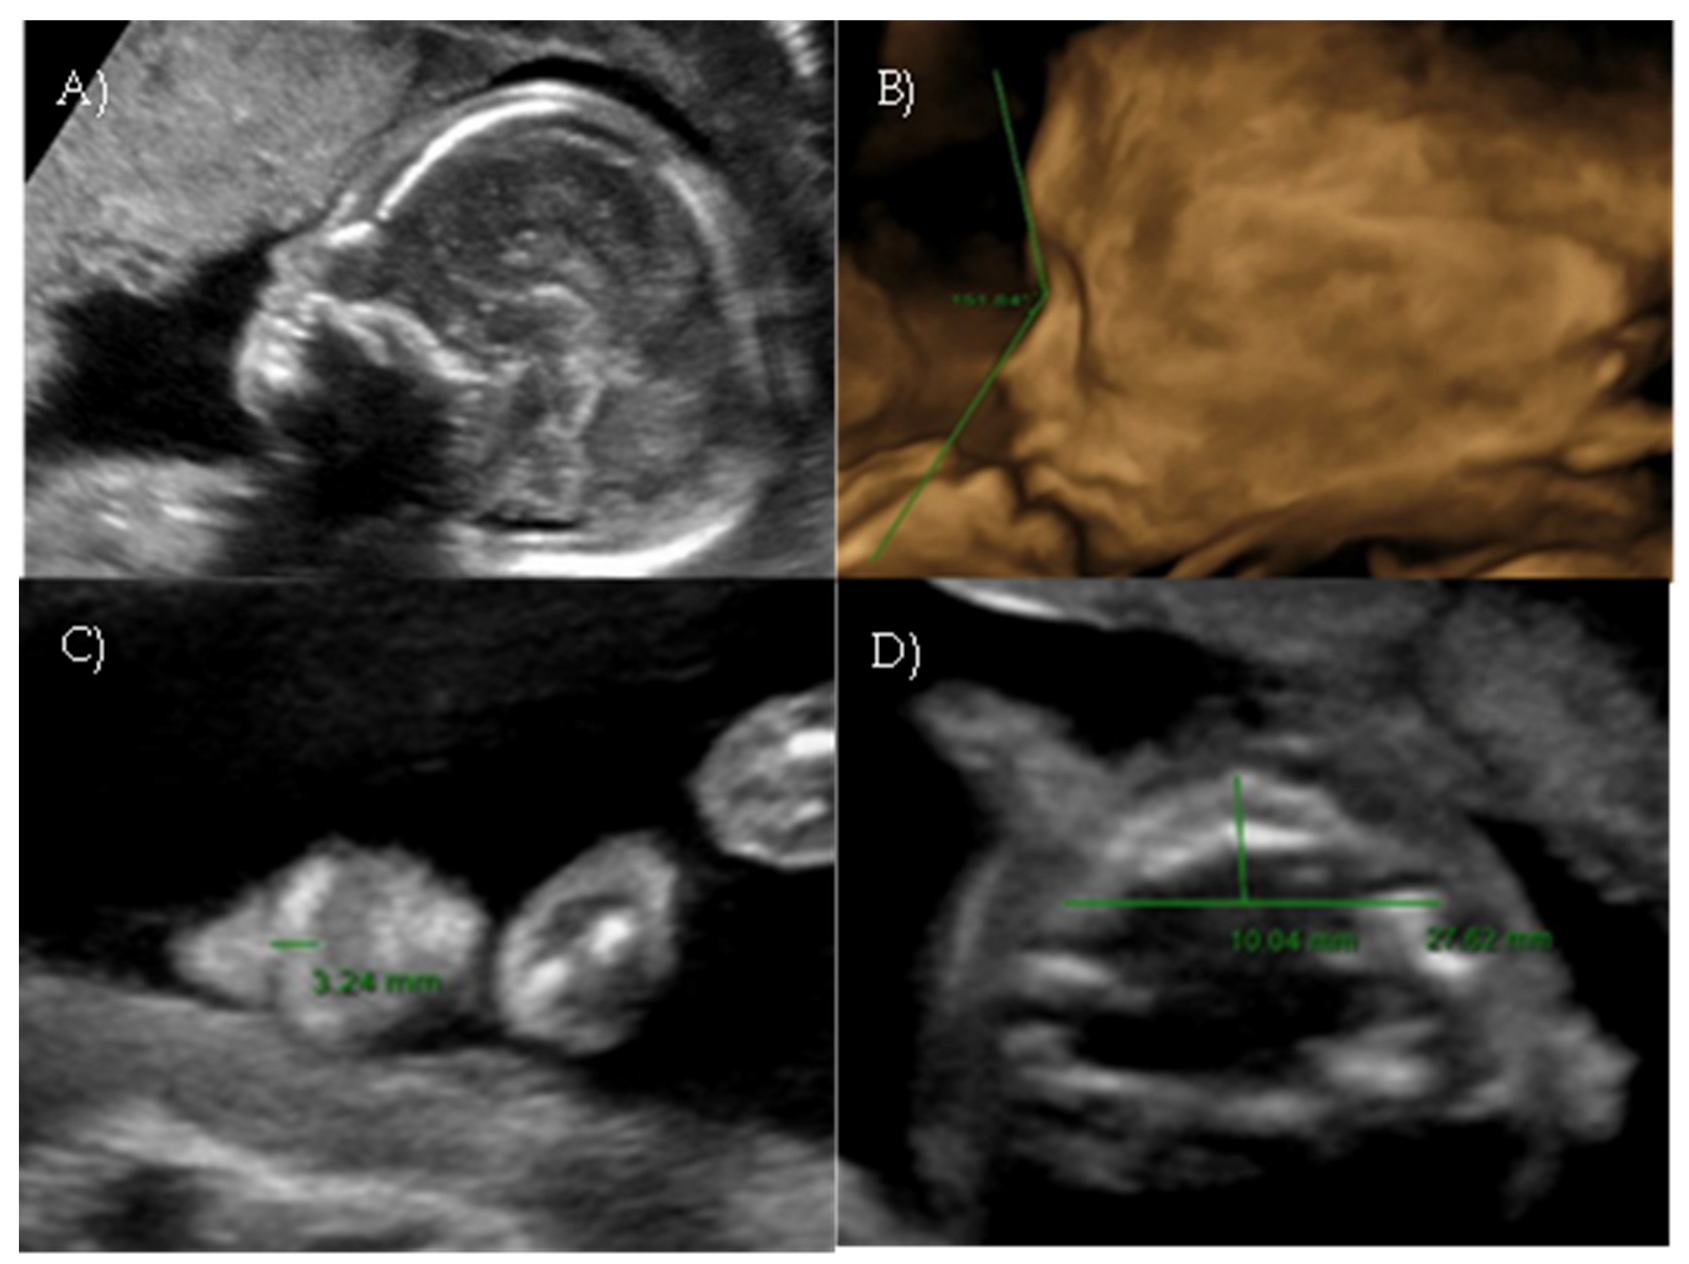

Her first-trimester combined screening for aneuploidies was low risk for trisomy 21, 18, and 13, and preterm preeclampsia. The nuchal translucency was within normal ranges (Figure 1A).

A detailed ultrasound scan was performed at 21 weeks and 1 day of gestation at our fetal medicine unit. Nasofrontal angle, nasal bone, and maxillary width were measured and compared to published references to unaffected fetuses at similar gestational ages [12,13]. Facial dysmorphism was further investigated by 3D scan (Figure 1B) through multiplanar mode and surface rendering, which allowed a more realistic representation of the fetal face, thus allowing characterization of the defect.

A flattened fetal facial profile with a nasal-frontal angle of 152.18° (cut-off: <143°, [14]), consistent with Binder-type maxillonasal dysplasia, was confirmed. To identify any other structural abnormalities, detailed examinations of the fetal anatomy and a fetal echocardiogram were conducted. No additional structural anomalies were identified (Figure 1C).

Figure 1. Case 1. (A) First-trimester 2D ultrasound Fetal profile. (B) Flat fetal profile, 21 weeks and 1 day, 3D reconstruction. (C) Nasal-frontal angle: 152.18°.